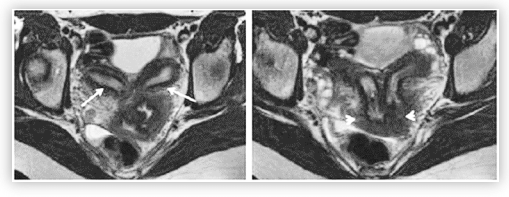

O exame abaixo representa o resultado de uma ressonância magnética pélvica .

A imagem assinalada, pelas setas é sugestiva de